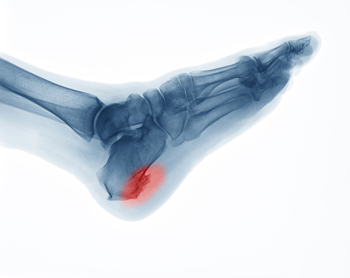

Heel spurs are bony protrusions that form on the bottom of the heel bone. They develop gradually from ongoing strain on the heel area, including repetitive stress activities like running or long periods of standing. The stress on the heel can lead to small tears in the tissues that attach to the heel, prompting the body to build extra bone as a defense mechanism. This becomes a heel spur. While not always painful, heel spurs can cause discomfort, especially when excessive pressure is placed on the heel. People with flat feet or high arches may be more prone to developing heel spurs. A podiatrist can diagnose heel spurs by conducting a physical examination and using imaging techniques like X-rays. Treatment usually involves non-surgical options, such as rest, wearing supportive footwear, or orthotic inserts designed to alleviate pressure on the heel. Surgery is only considered when symptoms persist despite these conservative treatments. If you believe you may have developed a heel spur, it is suggested that you schedule an appointment with a podiatrist for an exam and treatment.

Heel spurs are formed by calcium deposits on the back of the foot where the heel is. This can also be caused by small fragments of bone breaking off one section of the foot, attaching onto the back of the foot. Heel spurs can also be bone growth on the back of the foot and may grow in the direction of the arch of the foot.